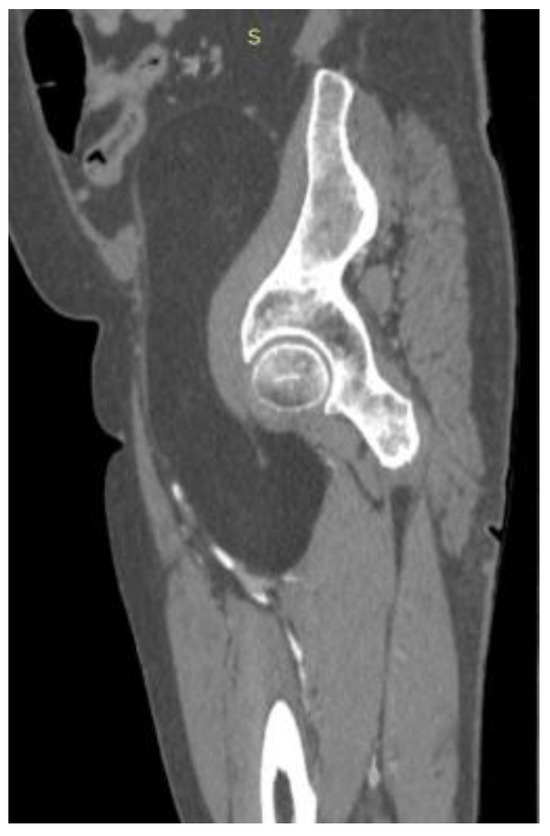

Asymptomatic Retroperitoneal Lipoma with Extension to the Right Anteromedial Thigh

2. Case Presentation